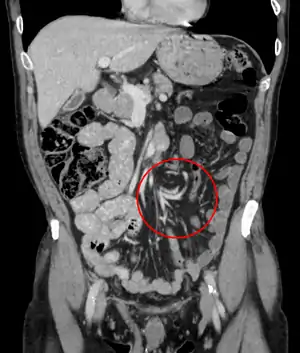

![]() | |

| Coronal CT of the abdomen, demonstrating a volvulus as indicated by twisting of the bowel stock | |

CT scan of a small bowel volvulus. It shows two juxtaposed segments of narrowing, which is the spot of mesentery rotation. The other signs indicate strangulation.

CT scan of a cecal volvulus